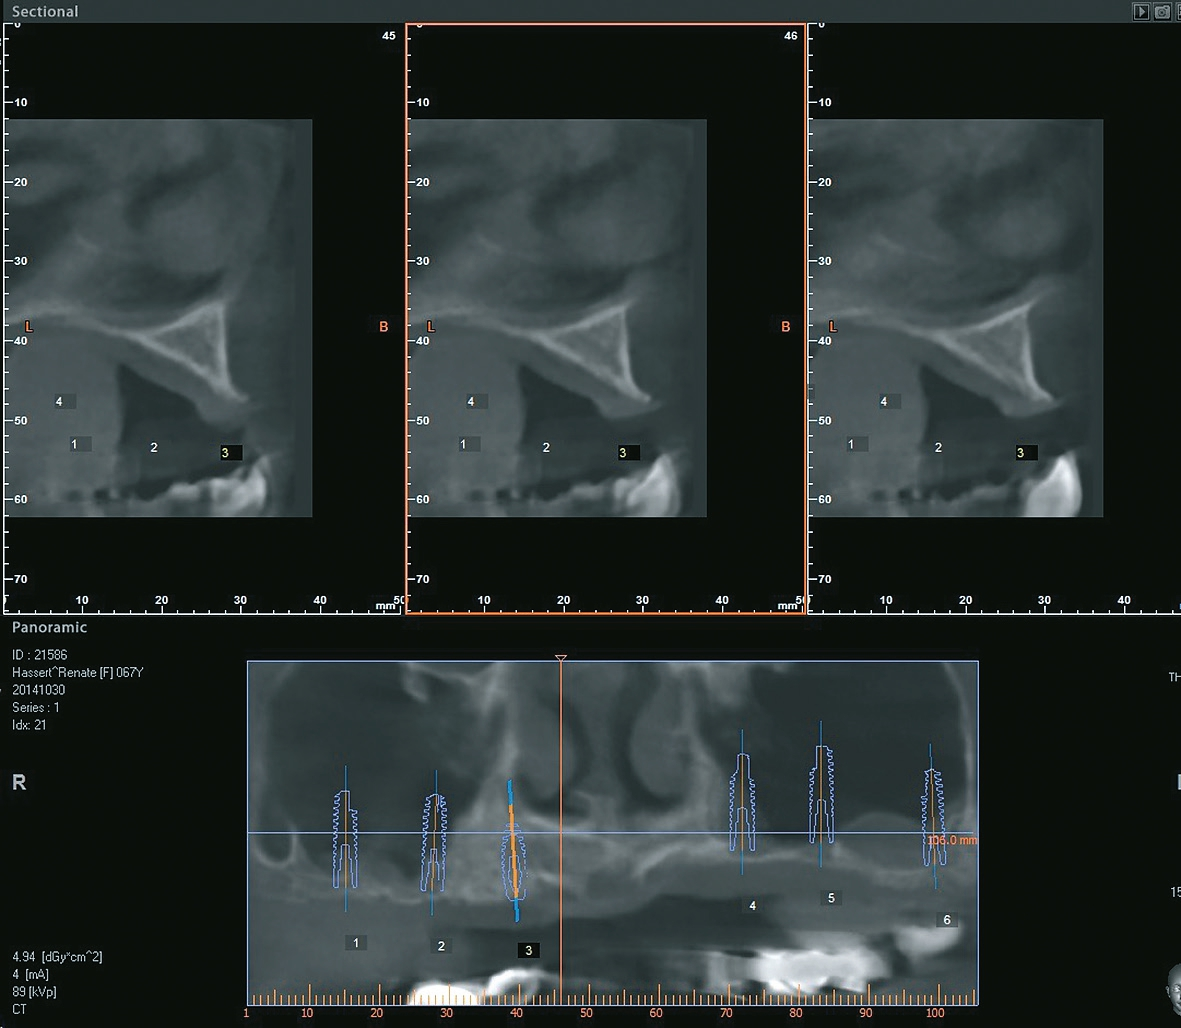

Vor dem zweiten OP-Eingriff nach 4 Monaten wurde im Labor eine Bohrschablone hergestellt. Zudem wurde ein DVT angefertigt, um im Sinne eines backward planning die idealen Implantatpositionen zu ermitteln. Bei Eröffnung des augmentierten Kieferbereiches zeigte sich eine gute Regeneration und Revaskularisierung des Knochens. Sechs Implantate konnten mit ausreichender Länge und passendem Durchmesser so in den augmentierten Bereich (Astratech EV®, Dentsply Sirona Implants, Mannheim) inseriert werden, dass sich eine gleichmäßige Pfeilerverteilung ergab (Abb. 7 u. 8).

Die besondere zahntechnische Herausforderung bestand nun darin, das Implantat über ein Abutment in die vorhandene Stegversorgung einzubeziehen. Die genaue Position wurde über eine Abformung mit Laboranalogen bestimmt, kontrolliert durch ein OPG (Abb. 21). Wieder wurde in situ mit einem Übertragungsschlüssel aus Pattern gearbeitet, um das neu zu fertigende Stegstück spannungsfrei anschließen zu können. Nach ausgiebigen Prüfungen wurde die Ergänzung gegossen und nach der Patientenanprobe an den bestehenden Stegbogen angelasert (Abb. 22a u. b, Abb. 23). Es folgte die Herstellung der endgültigen Sekundär- und Tertiärstruktur (Abb. 24). Bei dem hier vorgestellten Patientenfall wurde das Sekundärgerüst herkömmlich gegossen (Brealloy, Bredent, Senden). Lichthärtender Kunststoff sowie Konfektionszähne komplettierten die Arbeit, wobei die Ästhetikanprobe unverändert übernommen wurde.